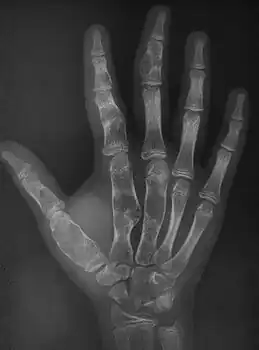

| Enchondromatosis in fingers | |

Enchondromatosis is the presence of multiple enchondromas, occurring as part of Ollier disease, Maffucci syndrome, or metachondromatosis.[3] It has a tendency to affect short tubular bones of the hands and feet, but can occur in long bones, shoulder blades and hips.[3] It presents with bone deformity, lumps, or broken bone, typically in a child.[2]

X-ray hand:Ollier disease in child